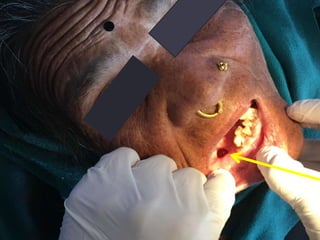

Intra-oral Examinations

• A swelling extending from distal of right mandibular canine to mesial

to left mandibular 1st premolar, of around 3×3 cm in size, without any

surface changes. On palpation, it was non-tender, bony hard with

egg-shell cracking present.

• A bony defect was present distal to right mandibular canine of around

1cm in diameter, with pus like discharge. On palpation it was tender.

• A fluctuant swelling present over right alveo-lingual sulcus of around

5×1 cm in dimension with no surface alterations and was fluctuant on

palpation.

• Generalized gingival recession present.

Intra-oral Examinations • Aswelling extending from distal of right mandibular canine to mesial to left mandibular 1st premolar, of around 3×3 cm in size, without any surface changes. On palpation, it was non-tender, bony hard with egg-shell cracking present. • A bony defect was present distal to right mandibular canine of around 1cm in diameter, with pus like discharge. On palpation it was tender. • A fluctuant swelling present over right alveo-lingual sulcus of around 5×1 cm in dimension with no surface alterations and was fluctuant on palpation. • Generalized gingival recession present.